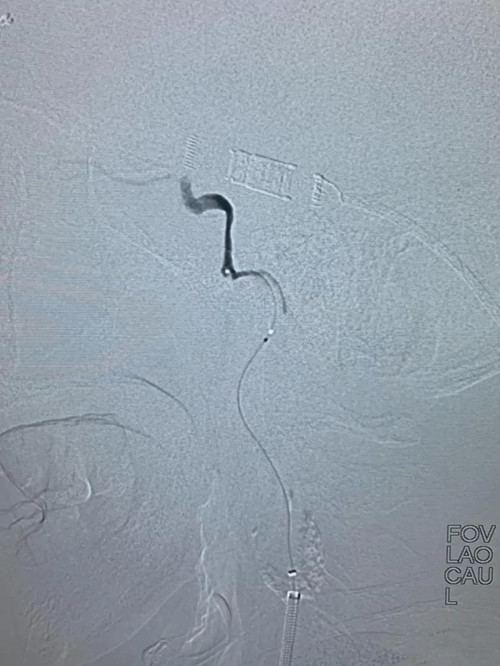

取栓程中,

导丝艰难寻找到闭塞颈内动脉的真腔

微导管进入颈内动脉颅内段

微量造影确认颅内血管闭塞